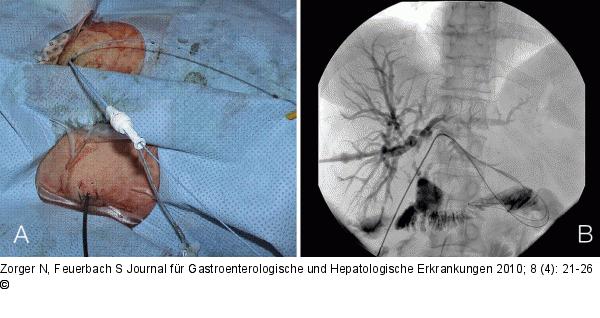

Abbildung 5a-b: Klatskin-Tumor 61-jährige Patientin mit Klatskin-Tumor. Z. n. operativer Anlage zweier peripherer biliodigestiver Anastomosen im Bereich der linken Leberkapsel. Nach Punktion des Gallensystems und Sondierung der ersten Anastomose Einbringen eines zweiten stabilen Führungsdrahts („Buddy wire“) zur Sicherung des perkutanen Zugangswegs vor Sondierung einer zweiten, ungewöhnlich peripher gelegenen biliodigestiven Anastomose. Der „Buddy wire“ soll verhindern, dass der Zugang während der Sondierung verloren geht |

61-jährige Patientin mit Klatskin-Tumor. Z. n. operativer Anlage zweier peripherer biliodigestiver Anastomosen im Bereich der linken Leberkapsel. Nach Punktion des Gallensystems und Sondierung der ersten Anastomose Einbringen eines zweiten stabilen Führungsdrahts („Buddy wire“) zur Sicherung des perkutanen Zugangswegs vor Sondierung einer zweiten, ungewöhnlich peripher gelegenen biliodigestiven Anastomose. Der „Buddy wire“ soll verhindern, dass der Zugang während der Sondierung verloren geht |